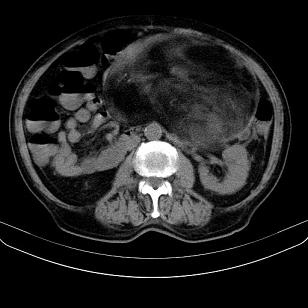

标题: CT21671:男,88岁,左上腹包块 [打印本页]

标题: CT21671:男,88岁,左上腹包块

患者因咳嗽而住院,自觉右上腹包块,无其他不适。

腹膜后高分化脂肪肉瘤

腹膜后脂肪肉瘤

腹膜生占位性病变,脂肪肉瘤可能。